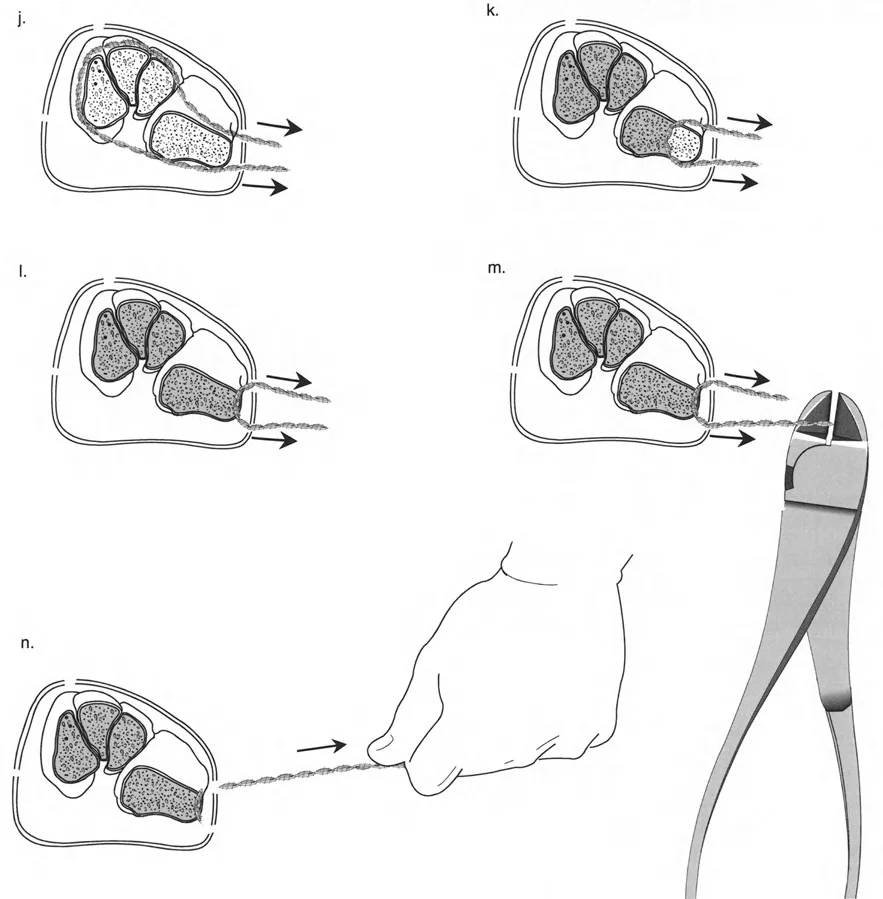

قيود الأسلاك والدبابيس في القاعدة 2

لتحقيق هذه الترجمة الضرورية والمقصودة بسلاسة باستخدام إطار دائري كامل الأسلاك، يلزم استخدام أسلاك الزيتون المعاكسة (counter-opposed olive wires). تعمل أسلاك الزيتون كقوى سحب ديناميكية، تسحب قطعة العظم على طول الحلقة أثناء فتح المفصلات. بدون أسلاك الزيتون، سيبقى العظم ثابتًا بينما تتحرك الحلقة عبر الأنسجة الرخوة، مما يسبب نخرًا شديدًا في الجلد.

على العكس من ذلك، إذا تم استخدام دبابيس نصفية (مسامير شانز)، فإنها تقيد العظم بطبيعتها بالحلقة. نظرًا لأن الدبابيس النصفية هي أذرع صلبة (مثبتة من طرف واحد بالحلقة ومغروسة في العظم من الطرف الآخر)، فإنها لا تسمح للعظم بالانزلاق على طول محور السلك. هذا يجعل أسلاك الزيتون غير ضرورية للترجمة في منشآت الدبابيس النصفية، ولكنه يتطلب من الجراح التأكد من أن الدبابيس النصفية قوية بما يكفي (عادةً دبابيس بقطر 5 مم أو 6 مم مطلية بهيدروكسي أباتيت) لتحمل لحظات الانحناء الناتجة عن الترجمة.

نصائح جراحية للمنشآت القريبة من المفصل

| تقابل الأسلاك | استخدم ما لا يقل عن سلكين زيتون متقابلين لكل قطعة إذا كنت تتجنب الدبابيس النصفية. | الأسلاك الزيتون الفردية ستسبب قصًا ودورانًا غير مرغوب فيه حول محور السلك. |